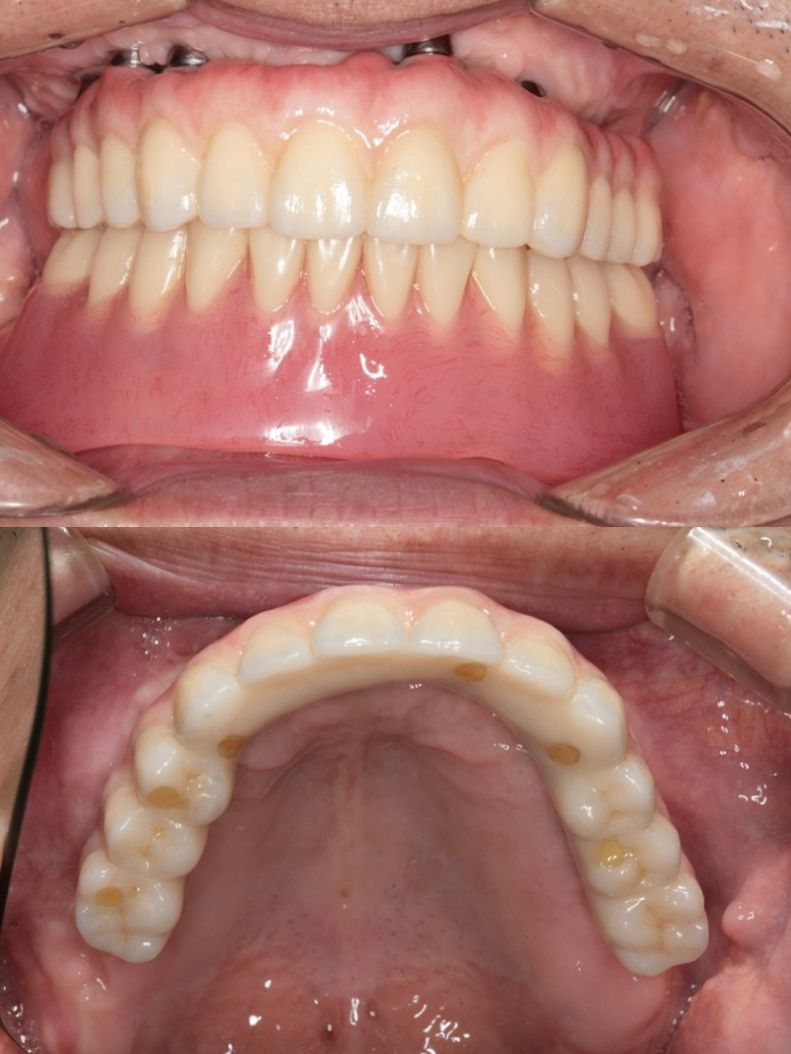

オールオン6(ボーンアンカードブリッジ)

インプラントオーバーデンチャー(ロケーターアタッチメントで義歯の維持)

| 年代 | 61歳 |

|---|---|

| 性別 | 男性 |

| 治療内容 | 上顎部分床義歯、下顎全部床義歯で咀嚼障害。高度の骨吸収(インプラント困難な症例) 上額のオールオン6インプラント治療。下顎インプラントオーバーデンチャーによる治療。 レントゲン診断、CT診断、補綴シミュレーション、血液検査、心電図、CT撮影ステント製作、サージカルガイド製作、治療用義歯、静脈内鎮静法抜歯、骨造成手術、サイナスリフト(上顎洞底挙上術)インプラント埋入、骨の治癒期間(4ヶ月)、静脈内鎮静法、2次手術、印象・咬合採得、インプラント上部構造装着、義歯装着、メインテナンス |

| 治療期間 | |

| リスク | 術中の不可抗力によるトラブル(出血など)、術後注意事項を守らないことによる疼痛、感染、上部構造装着後口腔内清掃を怠ったことによるインプラント周囲組織の炎症 |

| 副作用 | 治療後の口腔内清掃、及びメインテナンスを怠ったことによるインプラント周囲粘膜炎またはインプラント周囲炎 |

| 費用 | 4,400,000円(税込) (CT撮影診断、血液検査、心電図モニター、補綴シュミュレーション、治療用義歯、サージカルガイド製作、静脈内鎮静法、インプラント埋入、骨造成手術、サイナスリフト(上顎洞底挙上術)投薬、2次手術、印象・咬合採得、インプラント上部構造などを含む) |